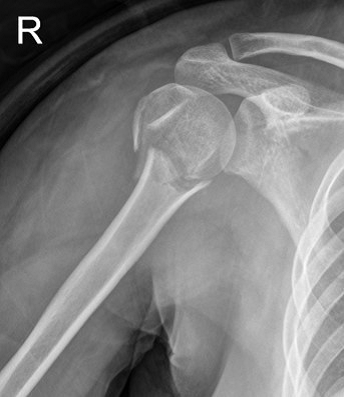

Figure 2: Simple radiographs of a 57-year-old woman who received far cortical locking system fixation. (A) Preoperative radiograph showing a displaced proximal humeral fracture. (B) Postoperative radiograph showing fixation with a straight intramedullary nail fixation. (C) A three-month postoperative radiograph showing union at the fracture site.